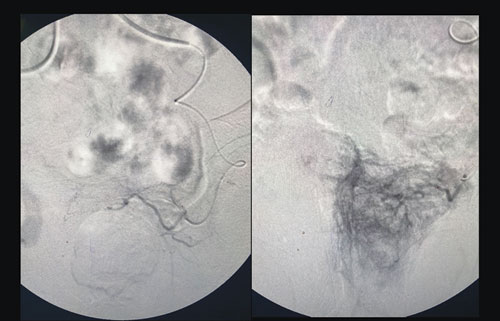

وقال الدكتور الغراس إن التدخل العلاجي بالأشعة التداخلية استغرق ساعتين تحت التخدير الموضعي، وتم فيه معالجة التضخم عبر صمام شريان البروستاتا، وهو علاج طفيف التغلغل يهدف إلى تحسين أعراض المجرى البولي الناجمة عن تضخم البروستاتا الحميد. مشيراً إلى أن جهود الفريق الطبي المعالج تكللت بالنجاح التام -ولله الحمد- دون أي مضاعفات، حيث خرج المريض من المستشفى في اليوم نفسه وهو بصحة جيدة، مؤكداً أن مراجعات المريض للعيادة بعد التدخل العلاجي للاطمئنان على وضعه الصحي أوضحت تحسنًا كبيرًا في حالته -ولله الحمد- بعد أن ساعدت تقنيات الأشعة التداخلية في إنهاء معاناته مع الاحتباس البولي.